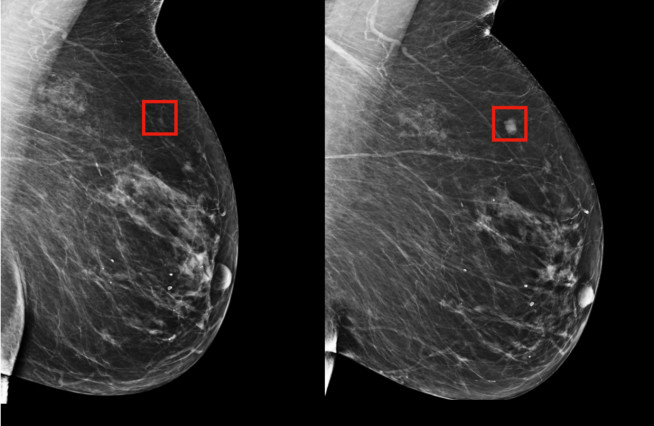

新的深度学习模型可以在癌症发病(右图)前四年,识别出乳腺癌风险(左图)(图片来源:MIT CSAIL)